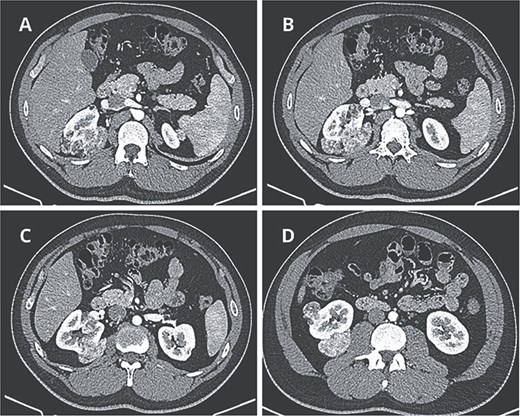

Contrast-enhanced computed tomography revealed at least six fat-density lesions in the right kidney, predominantly posterior, the largest measuring 3.5 × 4.7 × 6.1 cm, and two smaller lesions in the left kidney—findings consistent with AML (Fig. 1).

Preoperative CT scan. (A) Axial CT scan showing AML surrounding the right diaphragmatic crus. (B–D) Lesions composed of fat and soft-tissue densities in the upper, middle, and lower poles of the right kidney extending into adjacent retroperitoneal structures.